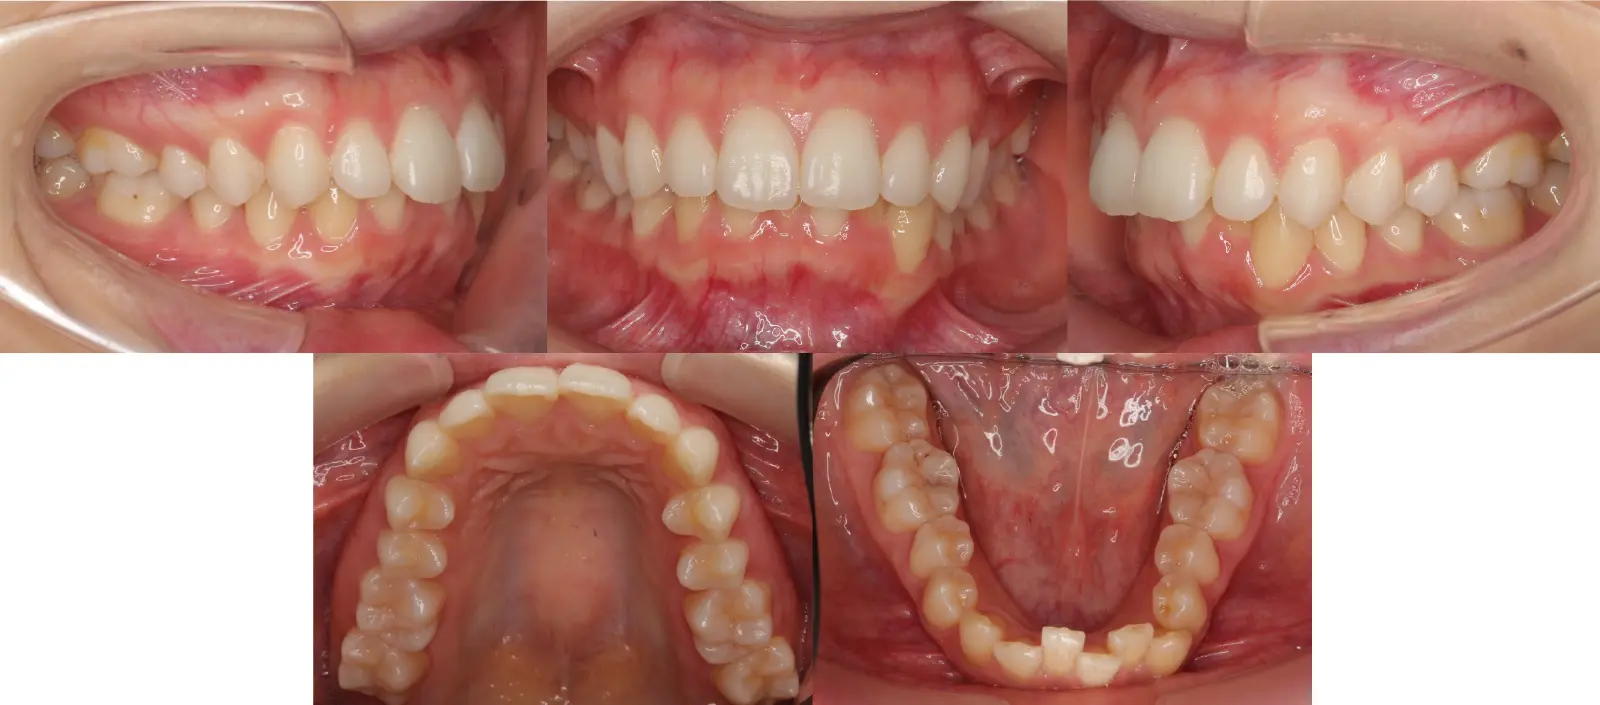

非対称を伴う叢生

八重歯

- 年齢

10代

- 治療期間

2年6ヶ月

- 治療回数

24回

- 治療に用いた主な装置

カスタムメイド型リンガルブラケット矯正装置(WIN)

歯科矯正用アンカースクリュー

- 治療費

1,200,000円(税別)トータル料金

- 抜歯部位

上下顎第一小臼歯4本